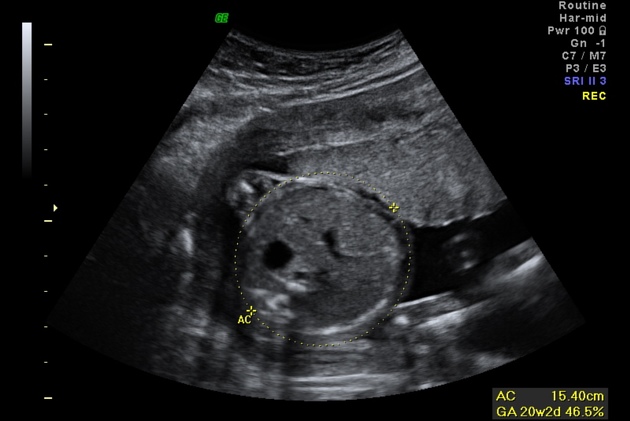

What measurement is taken in this view?

AC